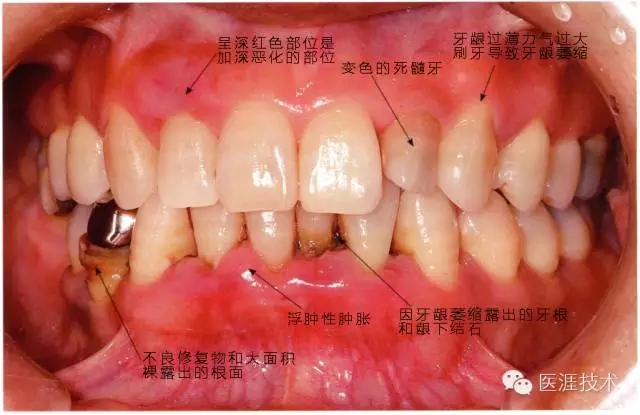

③患有牙周病的牙周組織是什么樣的呢?

牙周炎的患者主要有三種臨床癥狀,分別是牙齦炎癥、真性牙周袋的形成、牙槽骨吸收。牙齦呈浮腫性或纖維性腫脹、喪失對牙面的附著形成牙周袋。有時(shí)炎癥持續(xù)時(shí)間太長,會在接受牙周病治療后牙齦萎縮,牙根暴露。

在牙周袋內(nèi)形成混有血液的黑色齦下牙石。

患有牙周病的牙周組織的臨床照片

56歲牙周炎男性的臨床照片

正在服用高血壓藥中的56歲男性。菌斑控制得不好。通過牙周探診,全頜有4~6mm的牙周袋,在X光片中可以看到全頜中度牙槽骨吸收,磨牙處一個(gè)地方是重度牙槽骨吸收。通過比較牙周病進(jìn)展?fàn)顟B(tài),邊緣部有大范圍浮腫(發(fā)紅、腫脹),和纖維性肥厚。這也可能是服用中的降壓藥的副作用導(dǎo)致的。因?yàn)檠例l、牙槽骨比較厚,牙齦呈架子狀。

44歲牙周炎女性的臨床照片

44歲患有糖尿病病史(未治愈)。菌斑控制不良。通過牙周探診,全頜有4~8mm的牙周袋,在X光片中可以看到上頜前牙處中度牙槽骨吸收,磨牙處重度牙槽骨吸收。二次齲齒和根面齲齒也有發(fā)生。可以看到浮腫性腫脹,收到刺激后會出血。